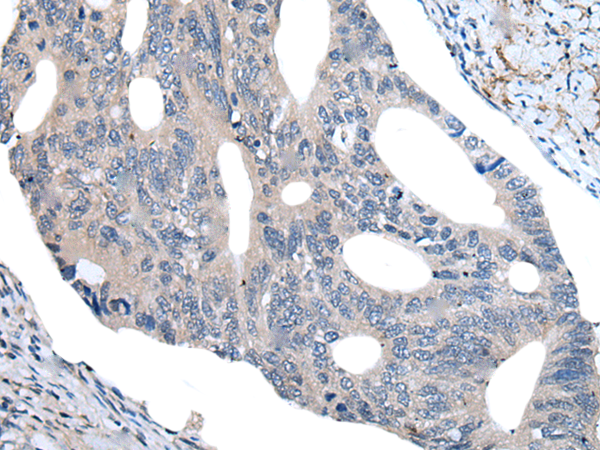

Applications:

ELISA, IHC

IHC positive control:

Human colorectal cancer and human tonsil

IHC Recommend dilution:

40-200